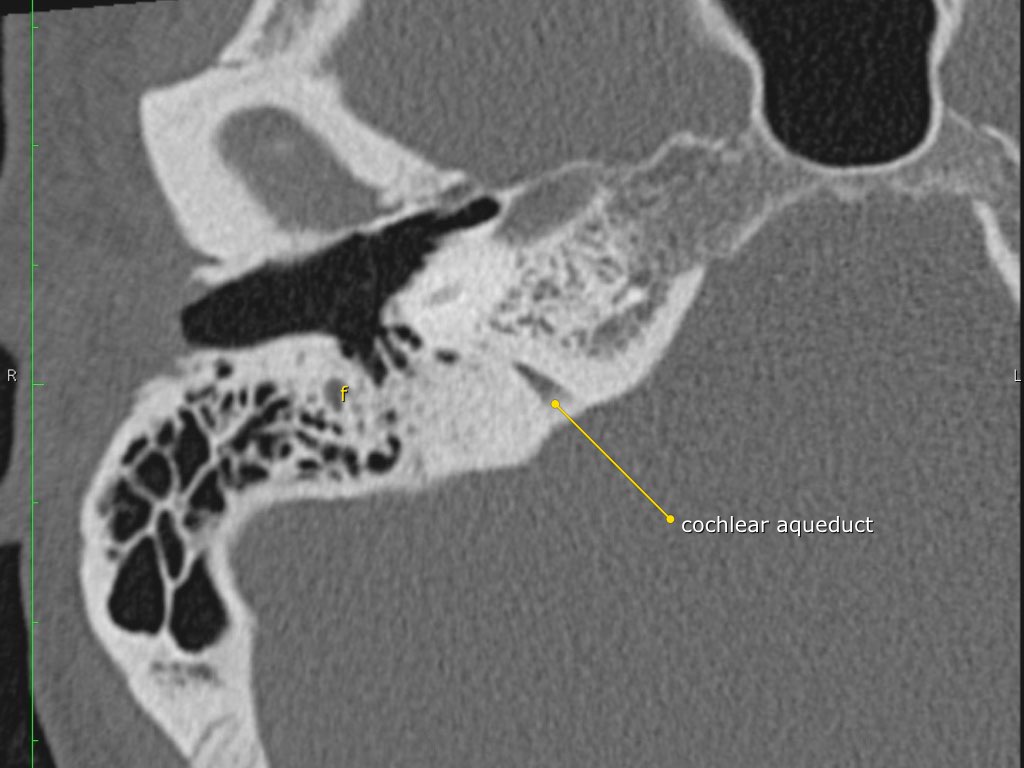

Trong bài tổng quan này, chúng tôi trình bày giải phẫu bình thường trên mặt phẳng cắt ngang (axial) và mặt phẳng cắt đứng ngang (coronal) của xương thái dương thông qua việc duyệt qua các hình ảnh.

Giải phẫu xương đá trên mặt phẳng cắt ngang (Axial)

Nhấp vào hình ảnh để phóng to.

Cuộn qua các hình ảnh.